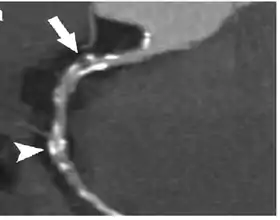

Coronary Computed Tomography Angiography (CCTA)

Computed tomography angiography (CTA), an imaging methodology using a ring-shaped machine with an X-Ray source spinning around the circular path so as to bathe the inner circle with a uniform and known X-Ray density. Cardiology uses are growing with the incredible developments in CT technology. Currently, multidetector CT, specially the 64 detector-CT are allowing to make cardiac studies in just a few seconds (less than 10 seconds, depending on the equipment and protocol used). These images are reconstructed using algorithms and software. Great development and growth will be seen in the short term, allowing radiologists to diagnose cardiac artery disease without anesthesia and in a non-invasive way.